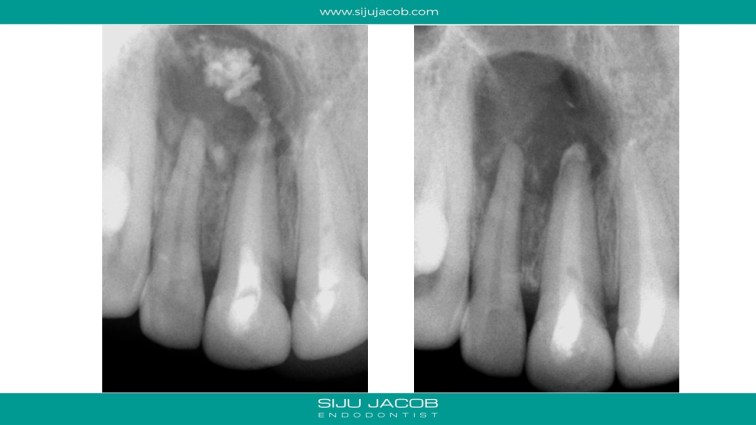

This patient had a large lesion in the right maxillary anterior region. The lateral Incisor tested vital. I decided to re-treat only the central Incisor. Despite several calcium hydroxide changes spread over 2 months, there was persistent drainage of pus. Instead of opting for the more radical option of endo on the lateral and immediate surgery, we decided to do decompression. The drainage stopped and the tooth was subsequently obturated. Patient recently came for some other work and I took a 5-year recall raiograph. It seems to be holding on for now. I was tempted to do the endo on the lateral on several occasions, but it always tests vital.